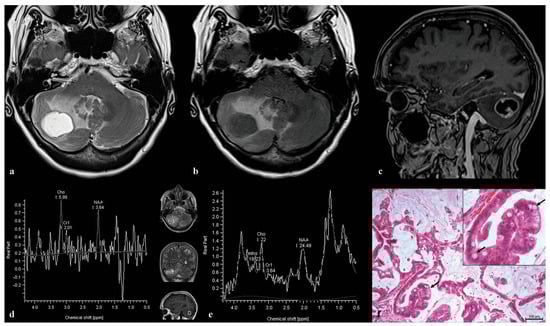

3.2. Patient 2